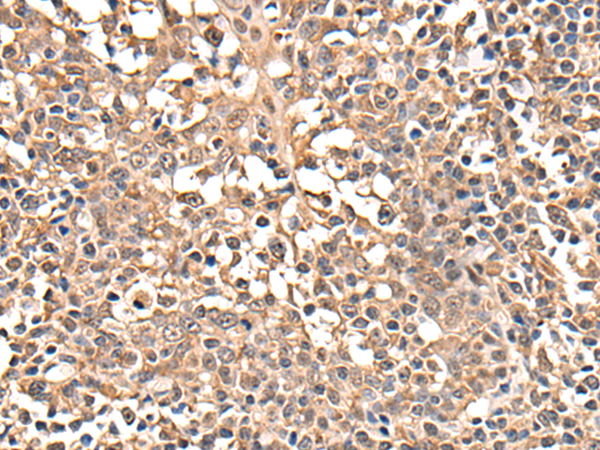

IHC positive control: |

Human thyroid cancer and human tonsil |